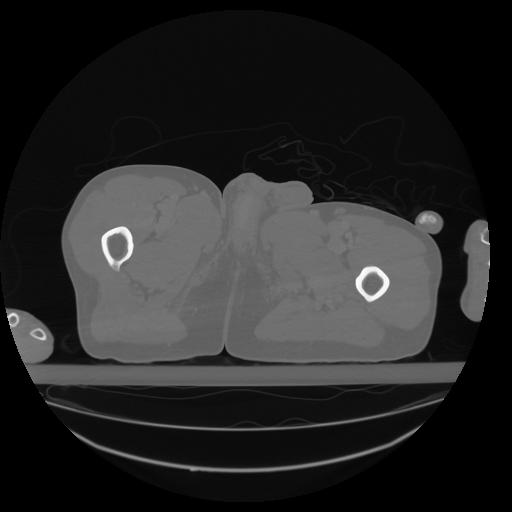

34 CUERPO,CE,Vol,1.0,CUERPO,,